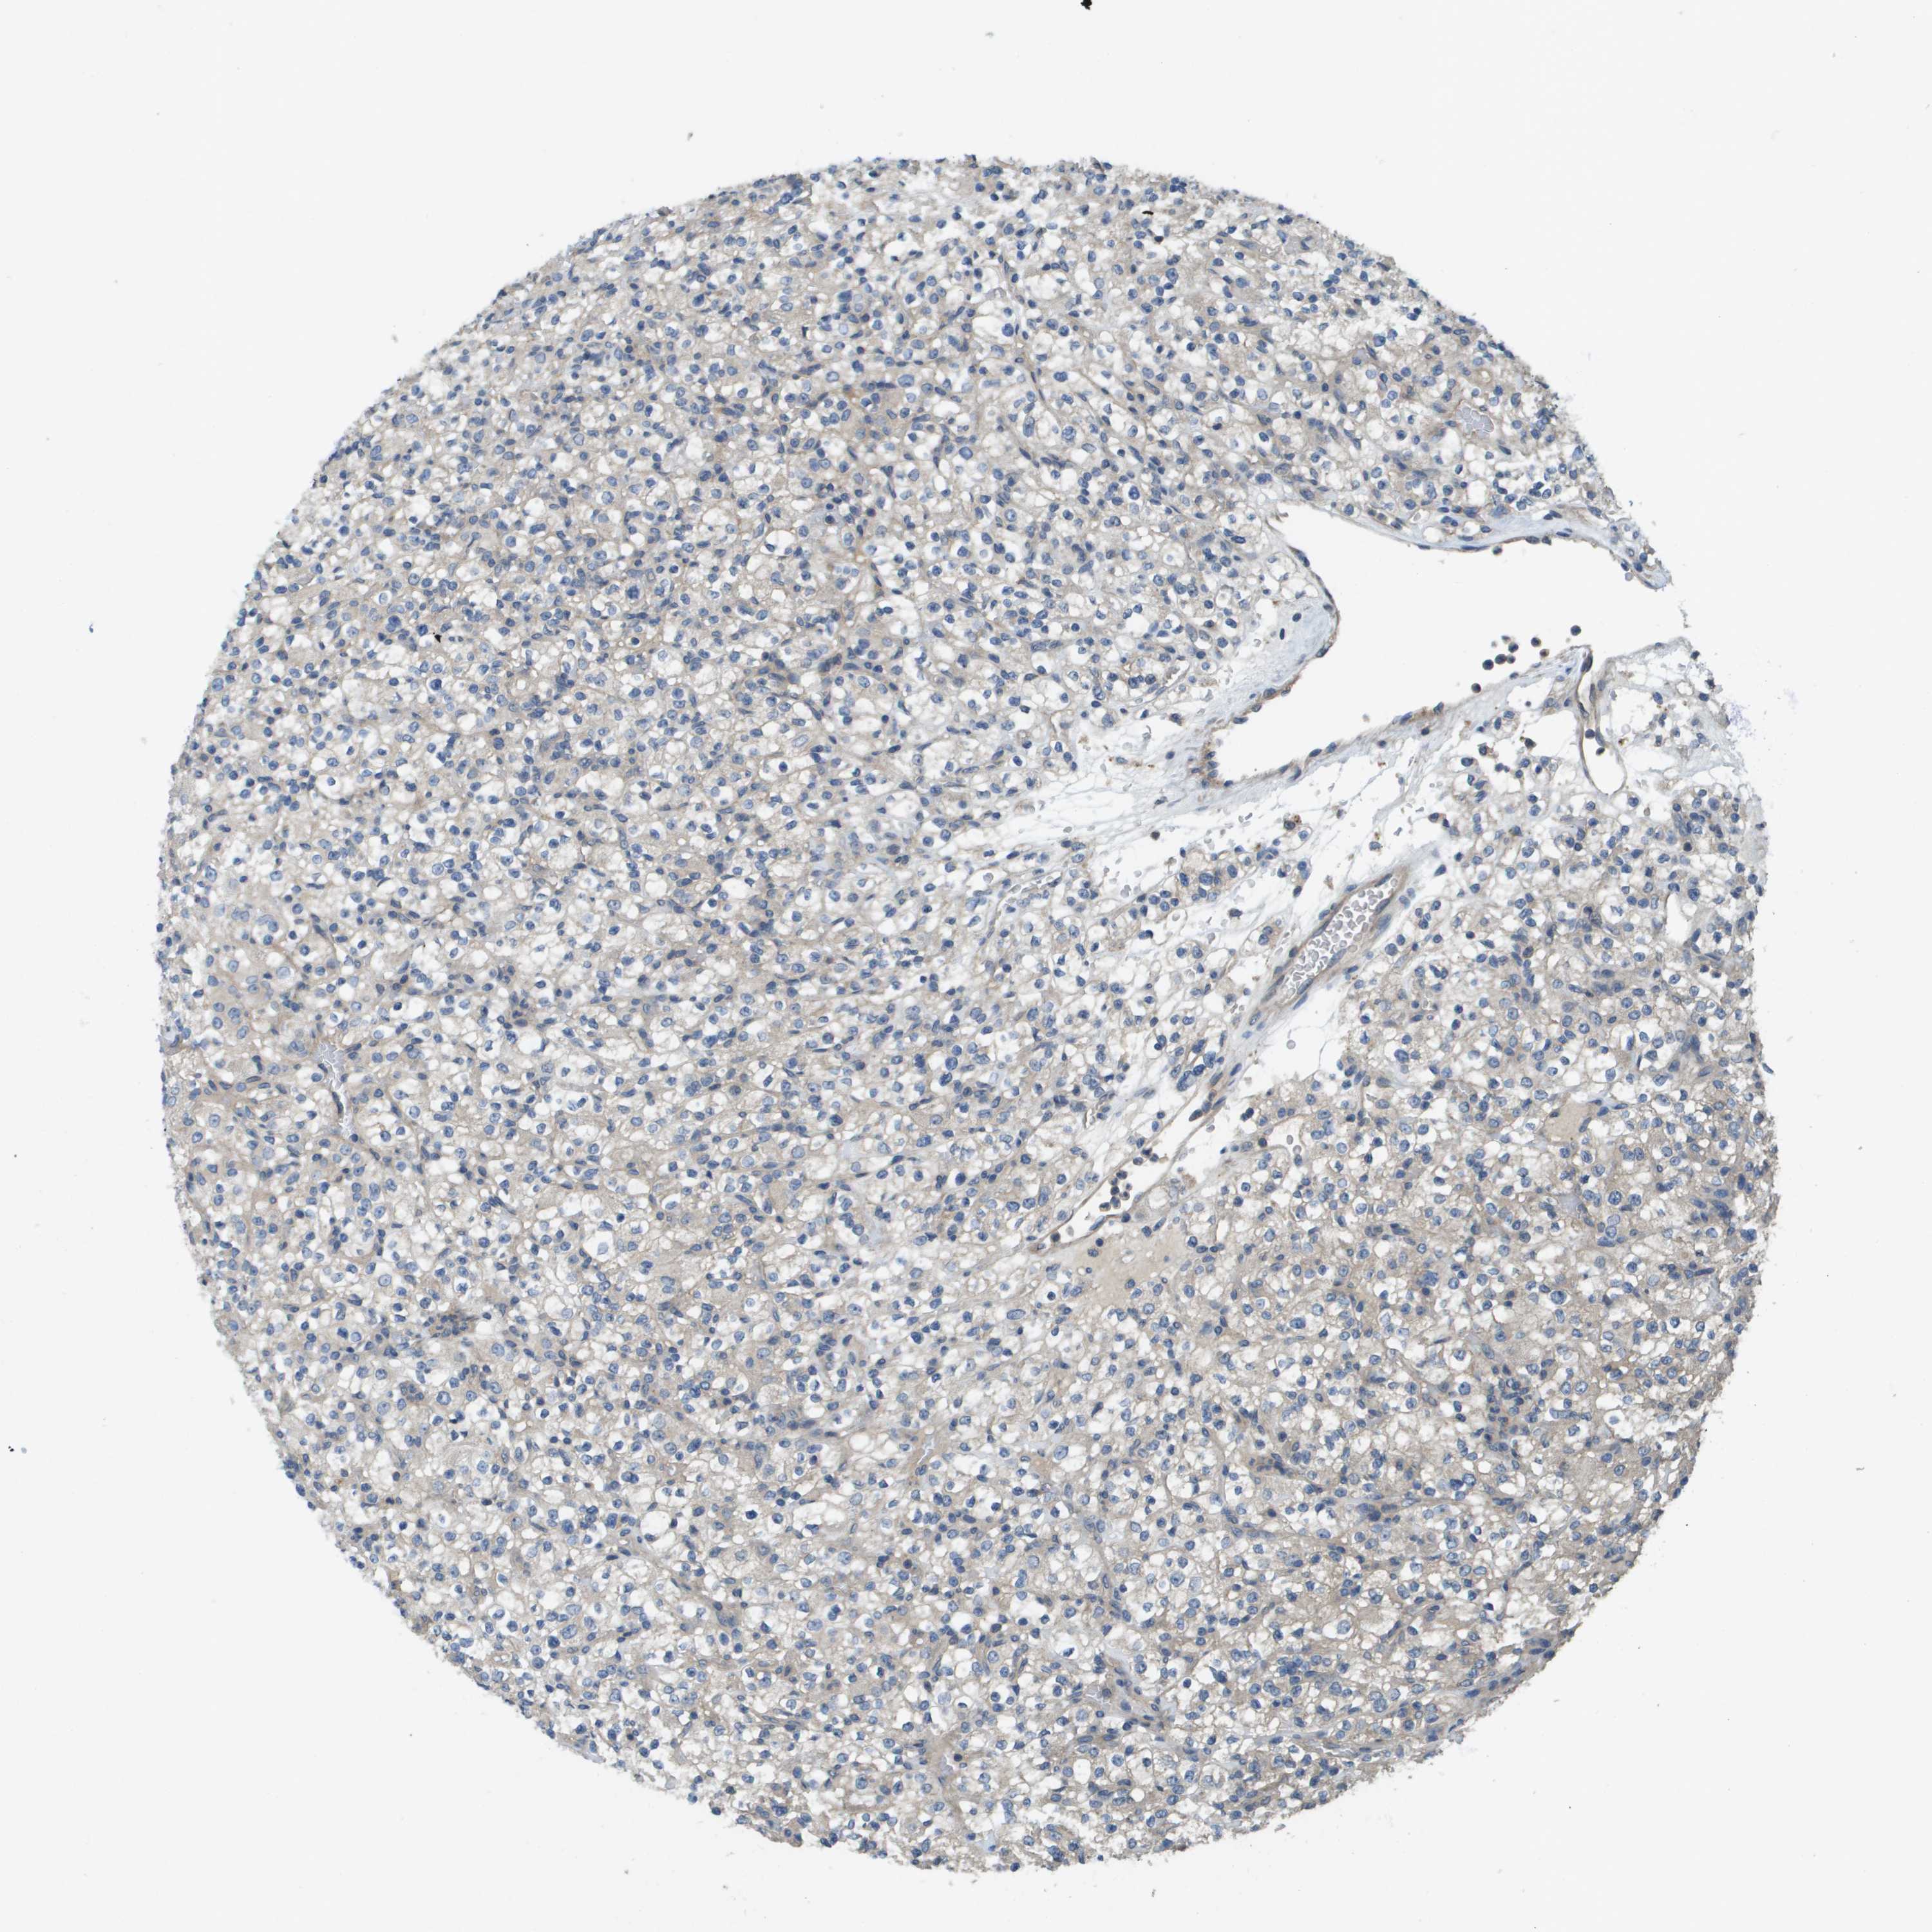

KIDNEY RENAL PAPILLARY CELL CARCINOMA (TCGA) - Interactive survival scatter ploti

The Survival Scatter plot shows the clinical status (i.e. dead or alive) for all individuals in the patient cohort, based on the same data that underlies the corresponding Kaplan-Meier plots. Patients that are alive at last time for follow-up are shown in blue and patients who have died during the study are shown in red.

The x-axis shows the expression levels (FPKM) of the investigated gene in the tumor tissue at the time of diagnosis. The y-axis shows the follow-up time after diagnosis (years). Both axes are complimented with kernel density curves demonstrating the data density over the axes. The top density plot shows the expression levels (FPKM) distribution among dead (red) and alive patients (blue). The right density plot shows the data density of the survived years of dead patients with high and low expression levels respectively, stratified using the cutoff indicated by the vertical dashed line through the Survival Scatter plot. This cutoff is automatically defined based on the FPKM cutoff that minimizes the p-score. The cutoff can be changed by dragging the vertical line or by entering a cutoff value in the square labeled "Current cut-off".

Under the Survival Scatter plot the p-score landscape (black curve; left axis) is shown together with dead median separation (red curve; right axis). Dead median separation is the difference in median mRNA expression between patients who have died with high and low expression, respectively. It is calculated as follows: median FPKM expression of dead patients with high expression - median FPKM expression of dead patients with low expression. This is intended to aid the user in visually exploring custom cutoffs and the associated p-scores and dead median separation.

Individual patient data is displayed and can be filtered by clicking on one or more of the category buttons on the top of the page. Categories describing expression level and patient information include: high, low, alive, dead, female, male and tumor stages. The scale of the x-axis can be toggled between linear and log-scale by clicking on the "x log" button. Mouse-over function shows TCGA ID, patient information and mRNA expression (FPKM) for each patient.

& Survival analysisi

Kaplan-Meier plots summarize results from analysis of correlation between mRNA expression level and patient survival. Patients were divided based on level of expression into one of the two groups "low" (under cut off) or "high" (over cut off). X-axis shows time for survival (years) and y-axis shows the probability of survival, where 1.0 corresponds to 100 percent.

KRT23 is not prognostic in Kidney Renal Papillary Cell Carcinoma (TCGA)

TCGA RNA samplesi

RNA-seq data is reported as average FPKM (number Fragments Per Kilobase of exon per Million reads), generated by the The Cancer Genome Atlas (TCGA) .

Normal distribution across the dataset is visualized with box plots, shown as median and 25th and 75th percentiles. Points are displayed as outliers if they are above or below 1.5 times the interquartile range. FPKM values of the individual samples are presented next to the box plot.

Average pTPM 2.4

Number of samples 282